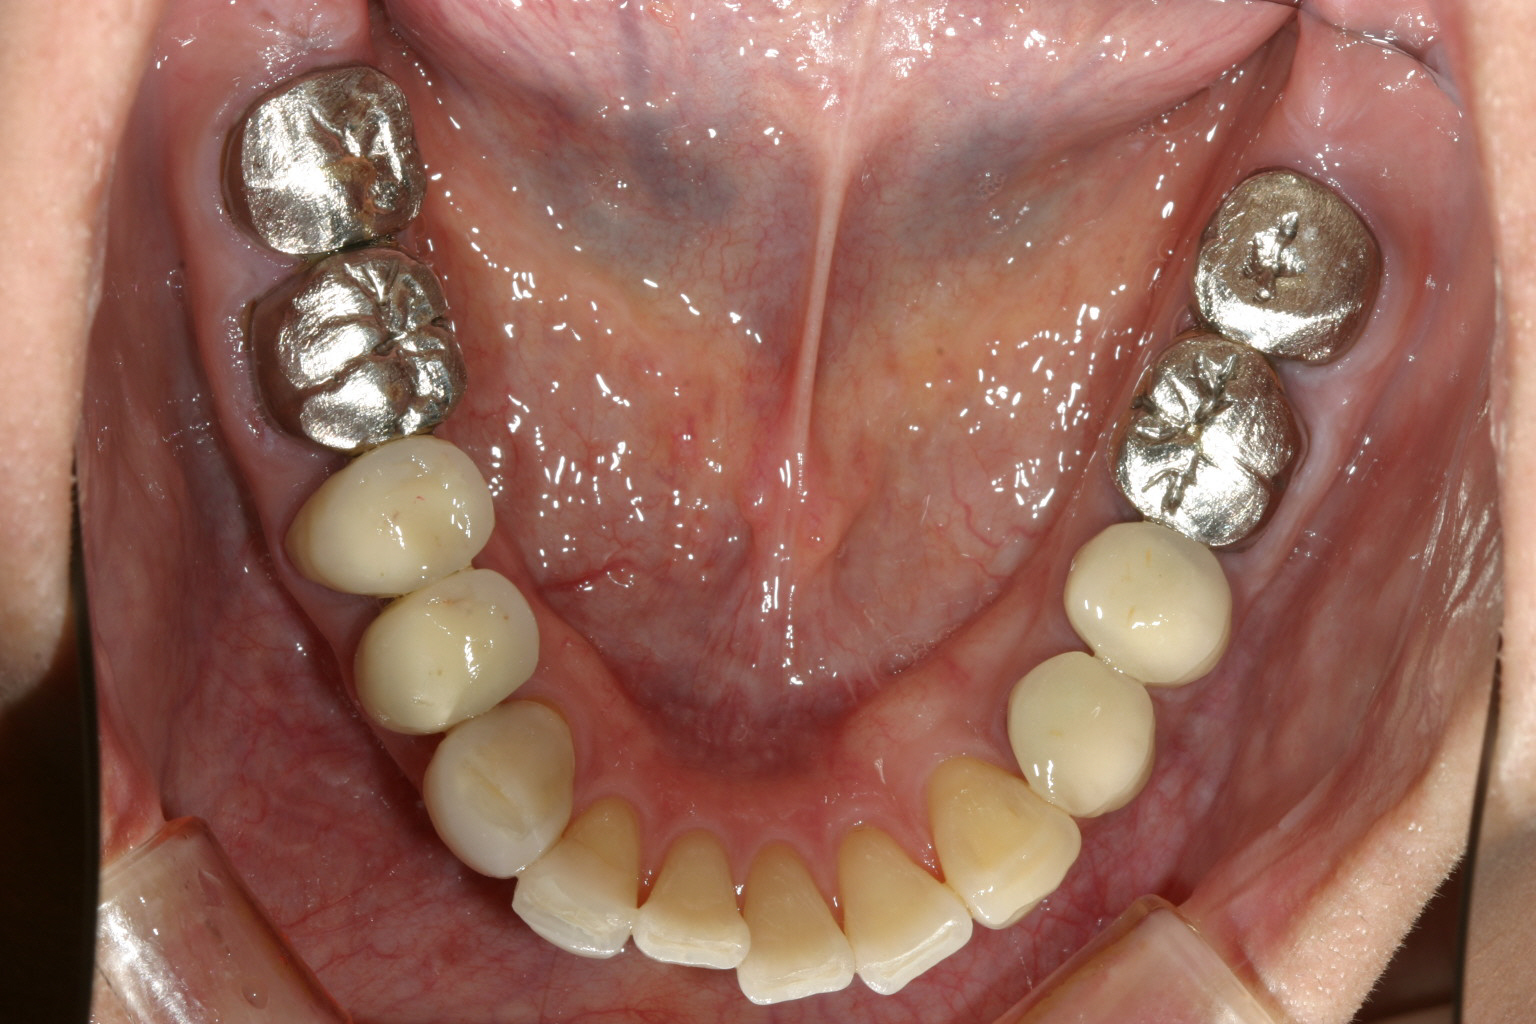

下顎は8本の臼歯を仮歯に変更して顎位を修正したのちマルチループワイヤーにてかみ合わせの調整を行う。 最初右にも左と同様のプラスティックレジン冠を入れるが顎位が右に戻る傾向があり咬耗激しく現在の様な金属冠に変更する。(全体的に少し高さを挙げて特に右側を沢山挙げる事により顎位が左へシフトさせる) アーチフォームもU字変更している。

下顎も矯正による咬合修正も終わり左右臼歯にジルコニア冠で8本補綴完了する

綺麗に咬合してます。 最初の正面観見て頂ければ正中が左にシフトし改善しているのが分かります。